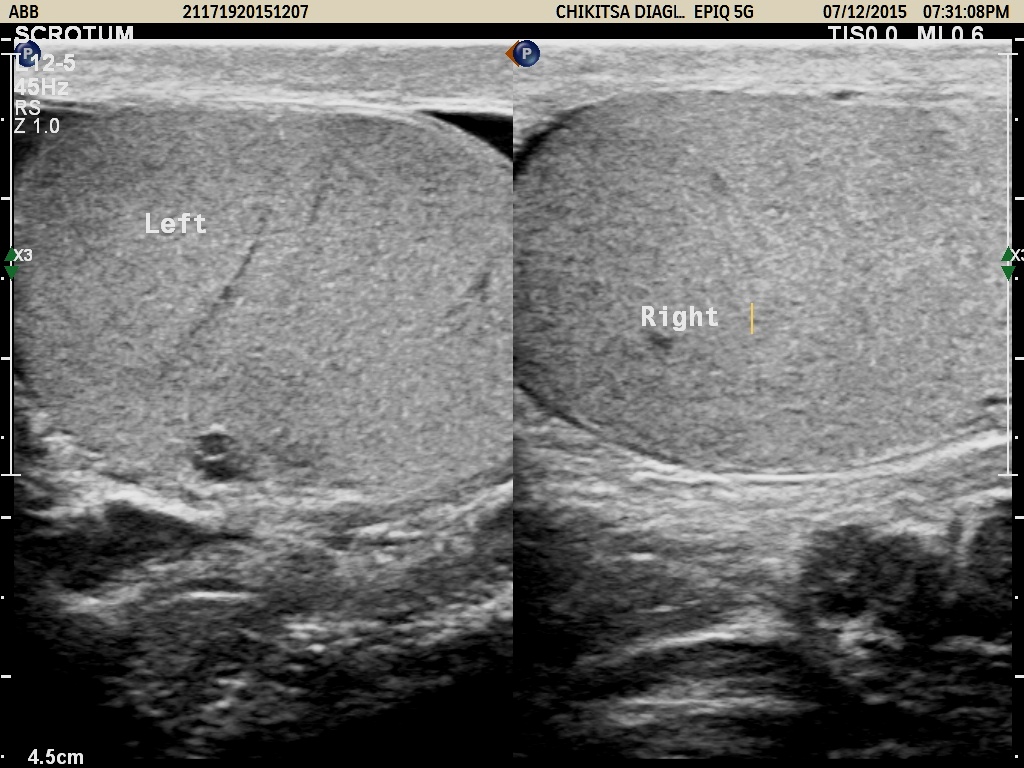

Testes & Scrotum Sonography

Ultrasound scanning involves the use of a small transducer (probe) to image the testes and the surrounding tissues.